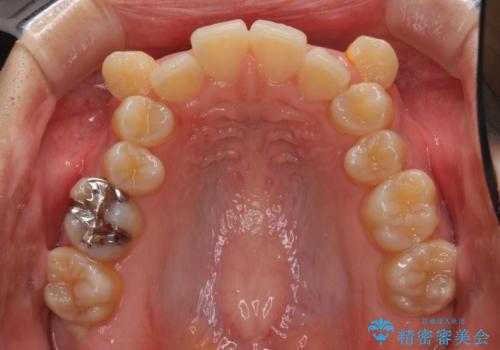

八重歯の抜歯矯正 補助装置を用いたインビザライン矯正

- 下の前歯のデコボコを気にして来院された患者様です。

来院当初、上顎の八重歯は気にしていらっしゃらなかったのですが、矯正治療をするのであれば、しっかりと治した方が良いと説明し、全顎矯正を行うこととしました。

八重歯の移動量が多く、インビザライン単体での治療は困難と判断し、補助装置により八重歯移動後にインビザラインを用いることとしました。

装着時間をしっかりと守ってくださったので、予定通りの期間で終了することができました。